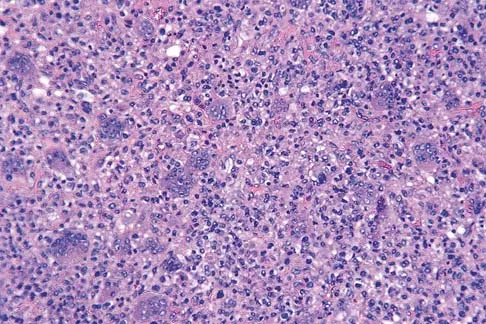

A 44-year-old man has right hip pain. Radiographs reveal a radiolucent lesion of the femoral head and neck. An MRI scan shows no extraosseous tumor extension. A histopathologic photomicrograph of the biopsy specimen is shown in Figure 5. The chance of metastatic disease developing from this lesion is approximately what percent?

The risk of pulmonary metastasis from a benign giant cell tumor is estimated to be 5%.